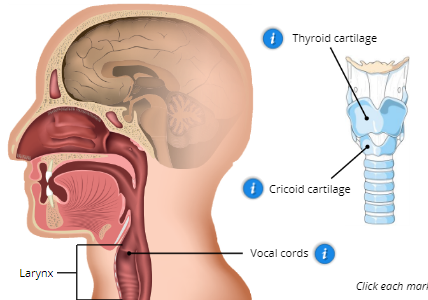

Larynx (voice box)

contains vocal cords and the thyroid and cricoid cartilage

Vocal cords

1. Upper: False Cords

2. Lower: True Vocal Cords

3. Glottis: opening between vocal cords that produce vocal sound

Thyroid Cartilage

Adams apple

Cricoid Cartilage

expands to allow large amounts of food to be swallowed